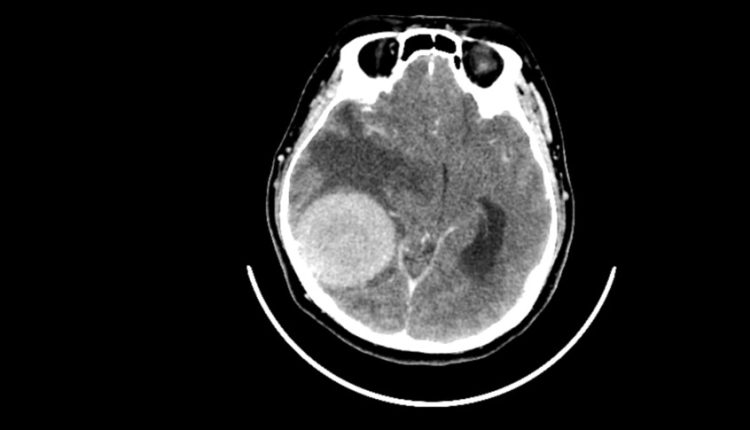

أعراض يومية شائعة قد تكون مؤشرات على أورام الدماغ

حذرت باحثتان من جامعة كوين ماري في لندن من أعراض يومية شائعة غالبا ما تُهمل “قد تكون في بعض الحالات علامات مبكرة على ورم في الدماغ”.

أكدت الباحثتان أن الكشف المبكر عن أورام الدماغ أمر بالغ الأهمية لتحسين فرص النجاة، حيث لا يعيش سوى ربع المصابين بأورام الدماغ في مراحلها المتأخرة أكثر من عام.